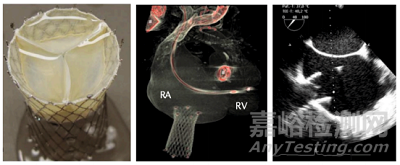

TricValve(P + F GmbH)

TricValve 是由澳大利亞 Pepperl+Fuchs(P+F)公司研發(fā)的一款三尖瓣異位置換產(chǎn)品。該產(chǎn)品由自膨式鎳鈦合金支架和牛心包瓣膜組成。救治性臨床應(yīng)用研究顯示了其具有較好的安全性,可減少腔靜脈反流量,改善臨床癥狀[73]。目前有兩項(xiàng)早期可行性臨床研究正在美國和歐洲開展(NCT03723239,NCT04141137)。

▲ Sapien XT 三尖瓣異位置換產(chǎn)品及其植入示意 (資料來源:Transcatheter interventions for tricuspid regurgitation - heterotopic technology: TricValve. EuroIntervention. 2016 Sep 18,蛋殼研究院)